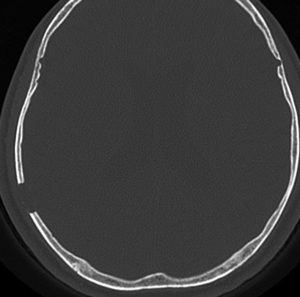

CTで典型的な頭蓋骨の打ち抜き像 punched out lesion が左頭頂骨にあります。これだけでLCHと診断がつくような画像です。

- 上の写真は,子供の右の頭頂骨にできたLCHで,頭部病変では最も多く見られるタイプです

- 頭蓋骨が丸く抜けるように破壊されるのでpunched out lesionと表現されます

- 頭蓋骨欠損がそれほど大きくないものは様子を見ます

- 自然に消失して治ってしまうことも多いです

- 単臓器単発型は無治療で経過をみるというのもよいでしょう